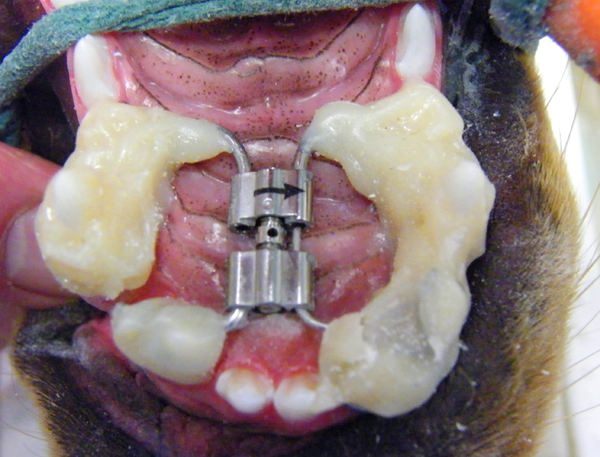

Ах да, кто интересовался фотографиями: их нет :( Ну в смысле фото "до" я не делала никогда (для меня это была не самая приятная тема), когда началось лечение мне вообще было не до того и я откровенно забыла, что есть люди интересующиеся этим. "После" делать тоже смысла нет- не самый светлый цвет, но вполне здоровый, зубы как родные, смотреть в общем не интересно, если не с чем сравнить. Было фото "забора" разве что, но туда жесть нужна явно, да и найти не могу чего-то. Еще есть снимок до установки штифтов, в середине лечения и переделки работы криворуких мудаков что занимались мной раньше. Качество какое есть, пардоньте :( Комментарии от врачей о состоянии моих зубов были в прошлом посте. Оказалось не так все дерьмово как выглядит.